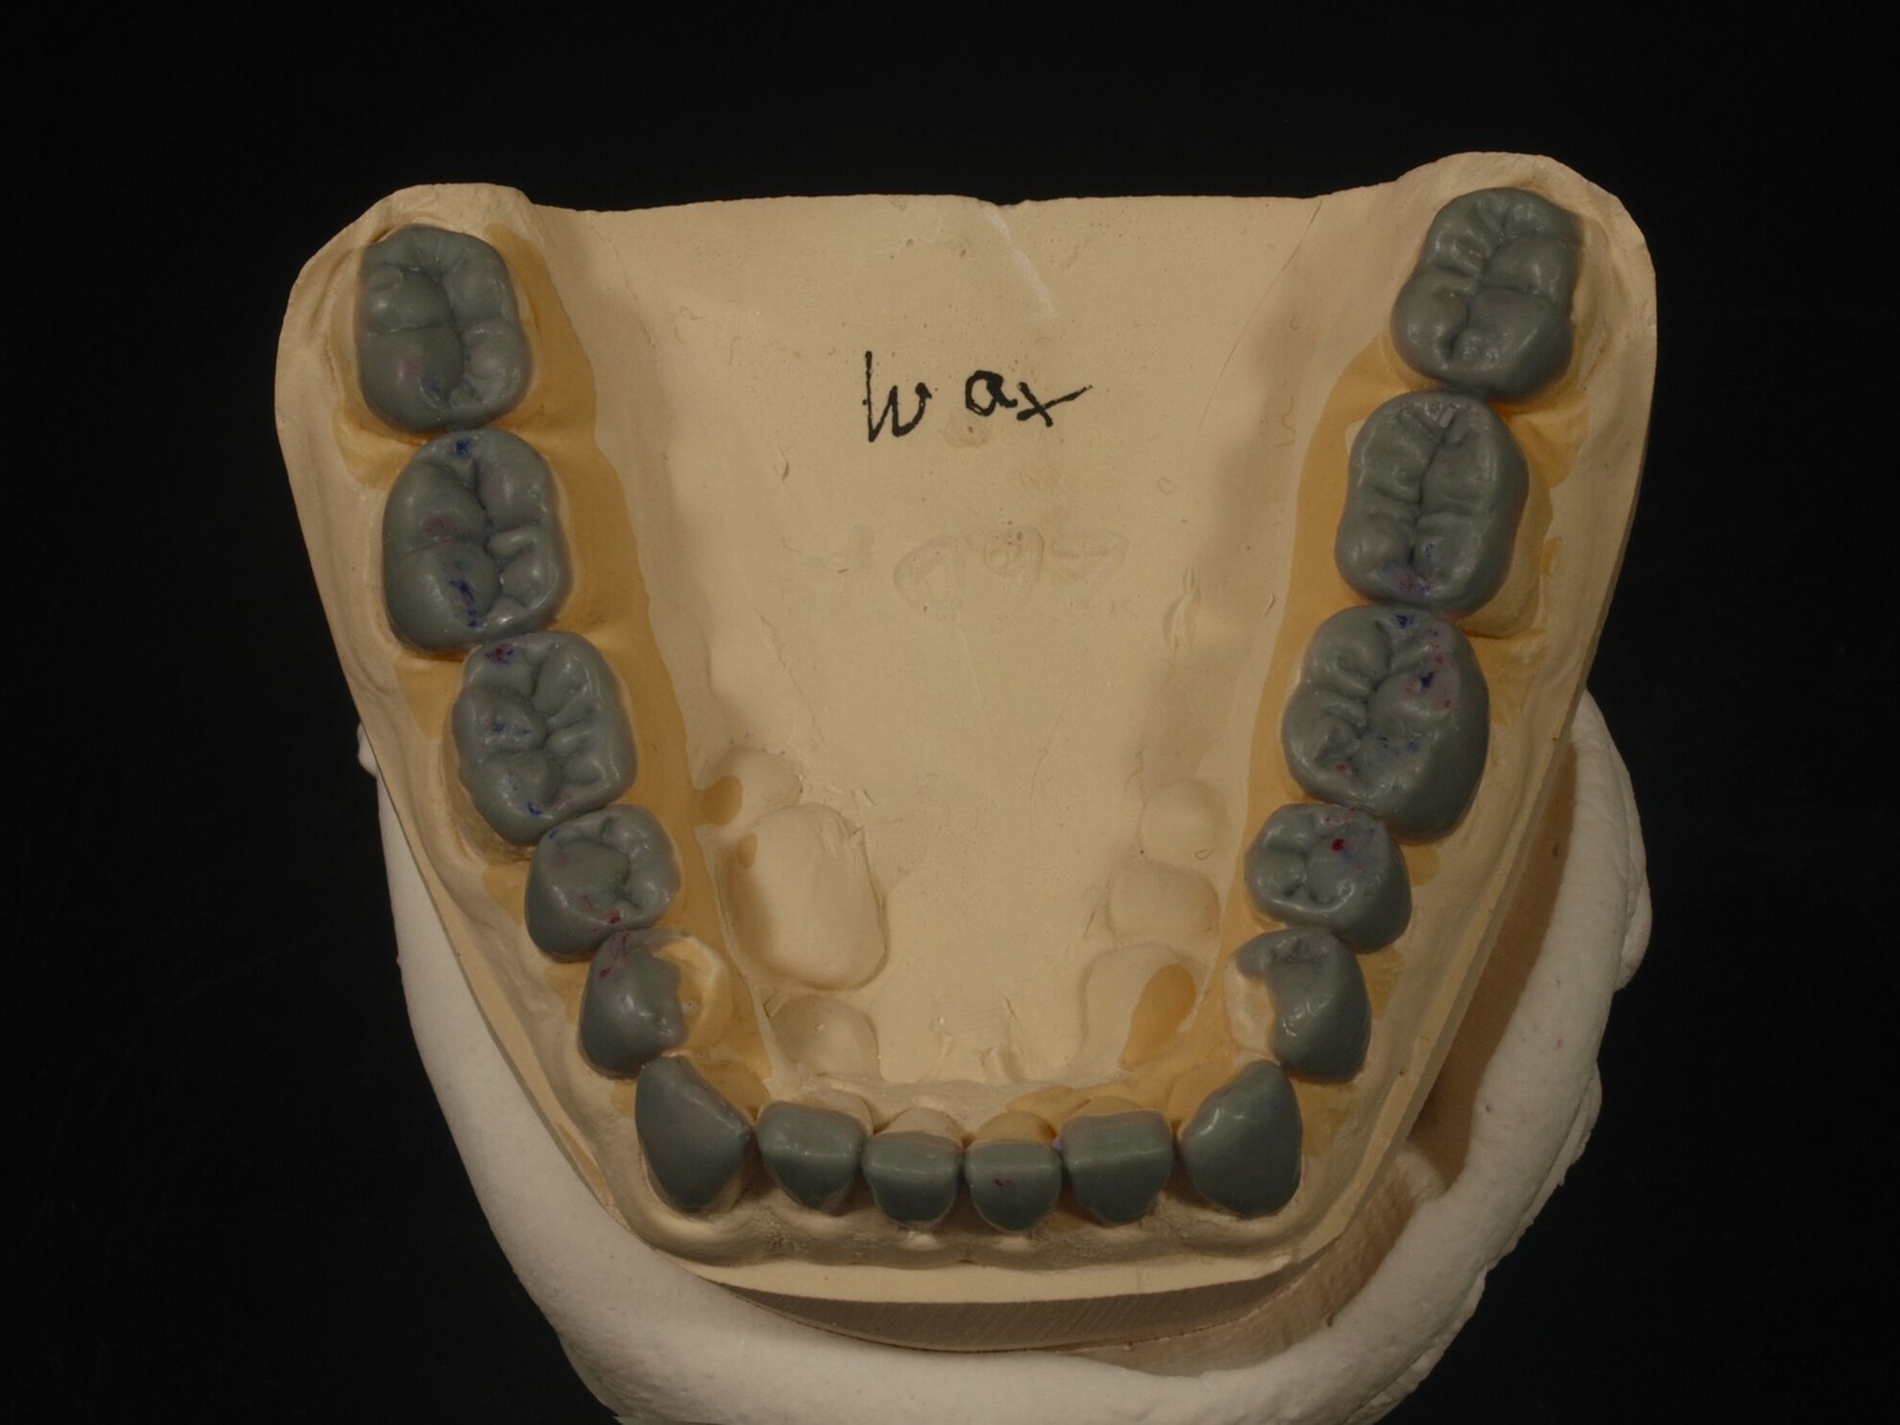

Auch erheblicher Zahnverschleiß lässt sich theoretisch mittels intraoral direkt verarbeiteter Komposit-Restaurationen behandeln. Dies erfordert dann allerdings zusätzlichen erheblichen zahntechnischen Vorbereitungsaufwand. An dessen Anfang stehen indirekte Präzisionsabformungen, die darauf beruhende Herstellung von Kiefermodellen und Duplikaten aus Superhartgips, deren schädelbezügliche Montage im Artikulator wegen der nachfolgenden Änderung der vertikalen Dimension.

Die Position des Unterkiefermodells wird zumeist auf der Grundlage von Registraten festgelegt. Die AWMF-Leitlinie zur instrumentellen Funktionsanalyse der DGFDT [Utz et al., 2022] empfiehlt, bei funktionsgesunden Patienten, die bei natürlicher Bezahnung in maximaler Interkuspidation gut abgestützt sind, diese Unterkieferposition in der Regel zu übernehmen (Empfehlung 25). Anders ist es, wenn zu wenige interokklusal abstützende Zähne vorhanden sind, eine sekundäre Unterkieferverlagerung vorliegt – etwa durch Zahnverschleiß – oder der Kauflächenkomplex insgesamt restauriert werden muss; in diesen Fällen sollte die vorliegende habituelle Okklusion in die restaurative Behandlung nicht übernommen werden. „In diesen Fällen hat sich die zentrische Kondylenposition, die dann zur zentrischen Okklusion wird, als Referenzlage bewährt (Empfehlung 26).“

Diese Simulation der Okklusion bildet die Voraussetzung für das nachfolgende Wax-Up der geplanten Zahnform als zahntechnische Planungsgrundlage. Das so ergänzte Kiefermodell wird anschließend dubliert, als Grundlage der Herstellung neuer Kiefermodelle in neuer Kontur, auf denen wiederum speziell verstärkte Formteile für die spätere intraorale Ausformung der Komposite erstellt werden. Die Ausformung der Restaurationen aus Kompositen und ihre Aushärtung erfolgen insofern zwar intraoral „direkt“, das Gesamtvorgehen ist aber an die gleichen zahntechnischen Vorarbeiten gebunden wie eine Therapie mittels indirekter Restaurationen. Solchermaßen hergestellte Restaurationen überstehen nach Untersuchungen der engagierten Kollegen aus Zürich drei Jahre in gutem Zustand [Schmidlin et al., 2009]; nach fünf Jahren ist der Zustand allerdings beeinträchtigt [Attin et al., 2012].